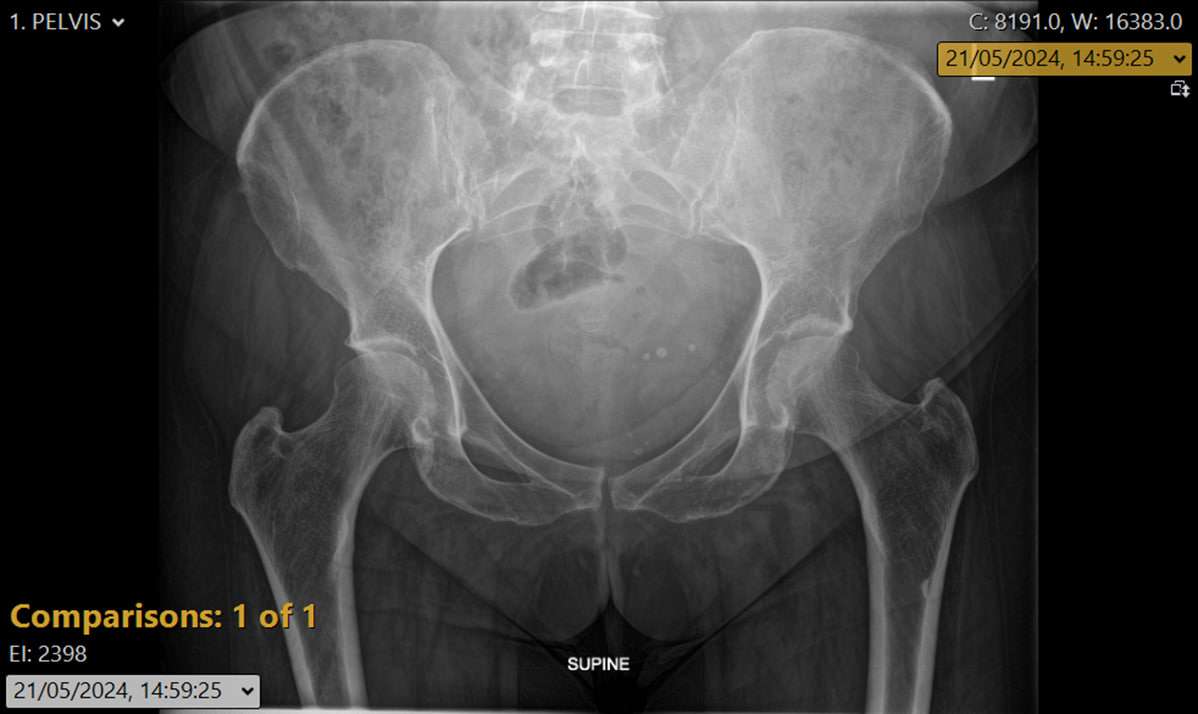

A 79-year-old female was referred by her general practitioner for consideration of total hip replacement due to severe bilateral hip and leg pain, resulting in an inability to sit comfortably, sleep adequately, or perform activities of daily living.

An urgent MRI scan of the lumbar spine demonstrated a large pelvic mass arising from the adnexal region, causing compression of the lumbosacral plexus. This explained the patient’s severe bilateral hip and thigh pain, which clinically mimicked meralgia paraesthetica.

- Maintain vigilance when hip pain presents with a normal X-ray — the pathology may be extra-articular or systemic in origin.